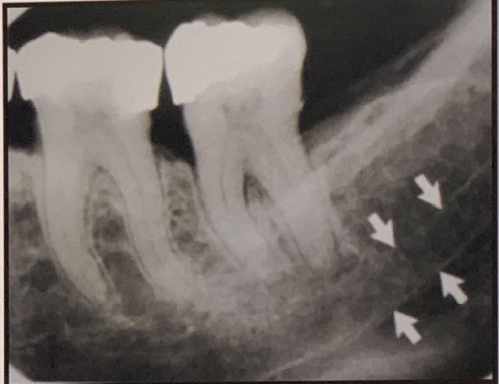

97. What is showing by arrow?

Nutrient Canals: carry a neurovascular bundle and appear as radiolucent lines of uniform width. most often seen on mandibular periapical radiographs running vertically from the inferior dental canal directly to the apex of a tooth or into the interdental space between the mandibular incisors. may appear as a small round radiolucency if they are oriented perpendicular to the cortex.